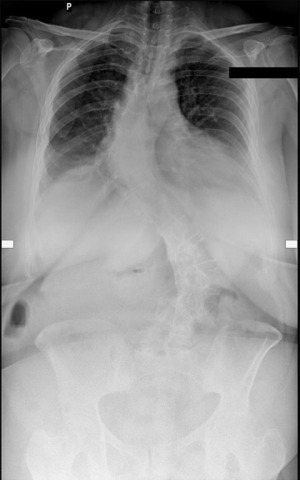

Radiographs obtained in 2023 (Figures 1,2) demonstrated progression of spine deformity with Cobb angle measurements of 60° in the thoracic region and 54° in the thoraco-lumbar spine with vertebral rotation. Computed tomography (CT) and magnetic resonance imaging (MRI) studies revealed fusion of the posterior elements of the vertebrae in Th5-L3, degenerative changes in Th12-L5 with herniated discs L3/L4, L5/S1. Secondary to the scoliosis, the spinal cord was pressed to the right wall of the spinal canal in section Th12-L3 and stenosis of the left intervertebral foramen with compression of the left intervertebral nerves at the level of L3/L4, L4/L5, L5/S1, which accounted for the patient’s neurological symptoms. The patient was diagnosed with type 2 adult scoliosis.